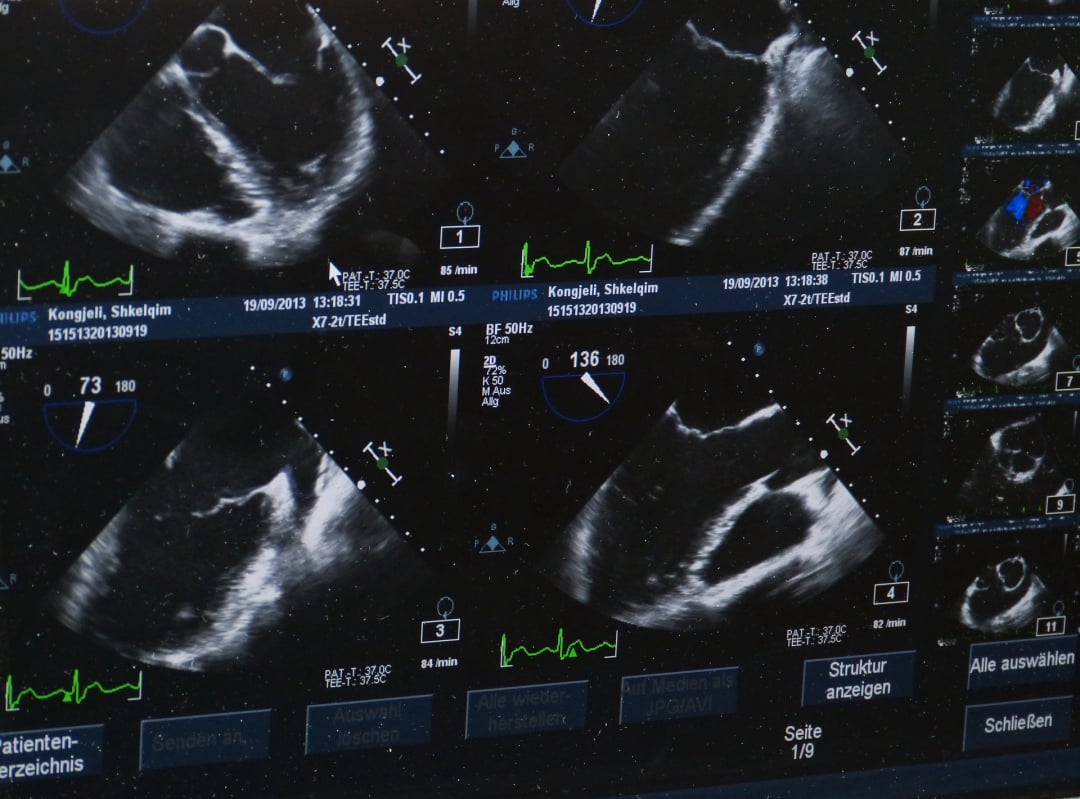

**Érezze Meg a Szíve Dobogását - Kardiológiai Szívultrahang Vizsgálatunkkal!**

Tudja meg, hogyan működik a szíve a részletekig szakértő kardiológiai szívultrahang vizsgálatunkkal! A modern orvostechnológia segítségével szívünk titokzatos világába nyerhet betekintést, és minden rezgését szinte érezheti.

Szívultrahang vizsgálatunk nem csupán egy egyszerű diagnosztikai eljárás - ez egy élmény, ahol a precíziós technológia és a tapasztalt szakemberek összefonódik a szív egészségének megőrzése érdekében. Lépjen be a szív frekvenciáinak világába, miközben mi minden apró részletre odafigyelünk!

Rugalmas időpontokkal és gyors eredményekkel várjuk Önt a szívultrahang vizsgálatunkon. Éljen a lehetőséggel, és kezdjen utazást szívének egészsége felé velünk! Hozza el szívét hozzánk, és hagyja, hogy a modern orvostudomány és a szívünk iránti szenvedélyünk gondoskodjon Önről. Egészséges szív, boldogabb élet - kezdje most!